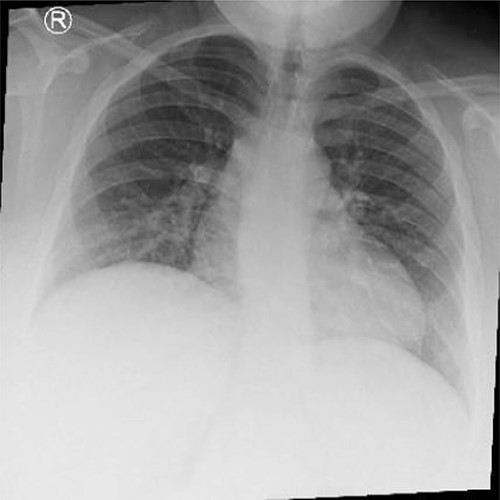

The patient underwent complete preoperative workup which includes clinical history, physical examination, complete blood count (CBC), coagulation profile, chemistry, lipid profile, endocrinology tests, US abdomen, chest X-ray, transthoracic echocardiography, computed tomography (CT) chest and CT abdomen, which showed reversal of intra-abdominal organs as shown in Figs 1, 2 and 3.

CT abdomen showing reversal of intra-abdominal organs with polysplenia.